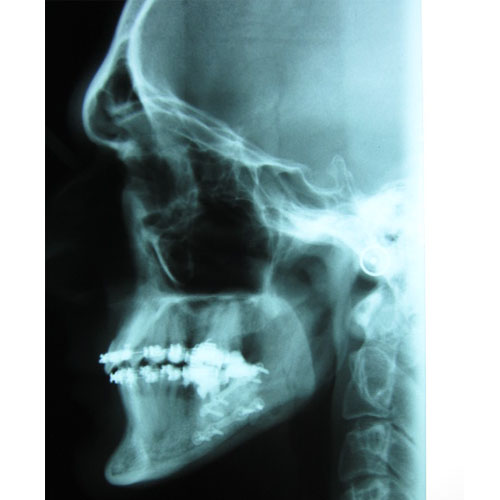

Leczenie ortodontyczne może być rozpoczęte w każdym wieku. Niektóre wady wymagają jednak leczenia kompleksowego, wielospecjalistycznego. Skojarzone leczenie dotyczy wad ortognatycznych, czyli wynikających z nieproporcjonalnej budowy szkieletu. Przykładem takiego leczenia jest leczenie progenii.